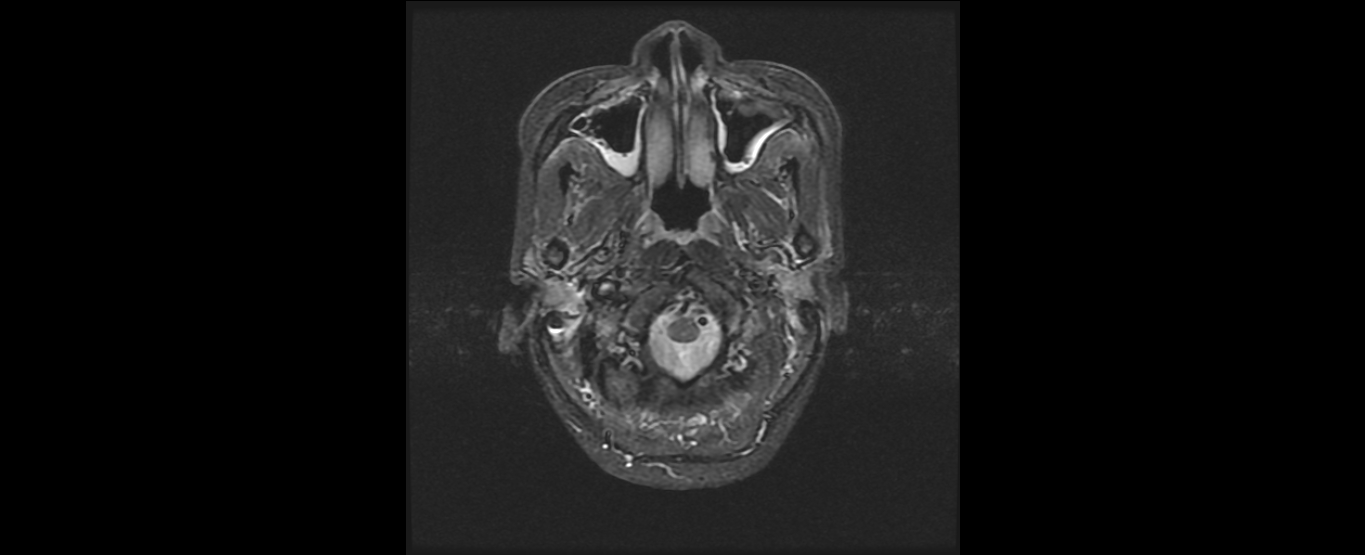

患者韦某某,女,37岁,2016年8月诊断为:鼻咽非角化未分化型癌(T2N2M0 III期),诱导化疗后行鼻咽癌根治性调强放疗,同期顺铂化疗,放疗结束后案辅助化疗。治疗结束复查见患者鼻咽肿物及颈部淋巴结均消退,疗效良好,目前随访1年患者各项检查指标完全恢复正常,已经恢复正常生活和工作。

放疗后鼻咽部MRI